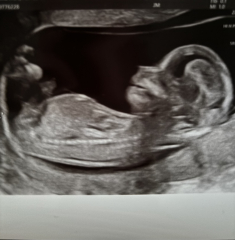

UnicornPrincessSarah · 17/06/2024 17:13

Hi ladys, hope we all doing well, I'm 16 weeks today and we had our gender scan today, confirming what I saw between the legs at my 12 weeks scan was in fact a penis, baby C is a boy

Due December 2024